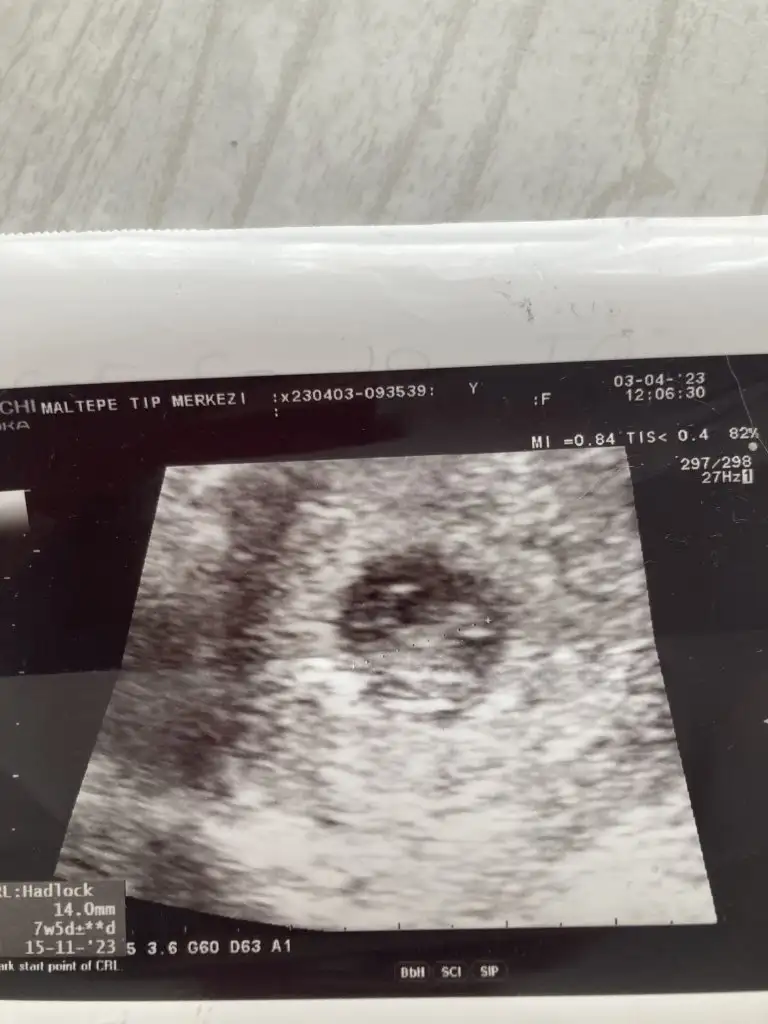

İlki 6+3 ikincisi 7+5 canım tahmin edenler oldu ama bakalım sen ne diceksin

6-7 haftalık ultrason resmini at canım ve karından mı vajinal mi onu yaz